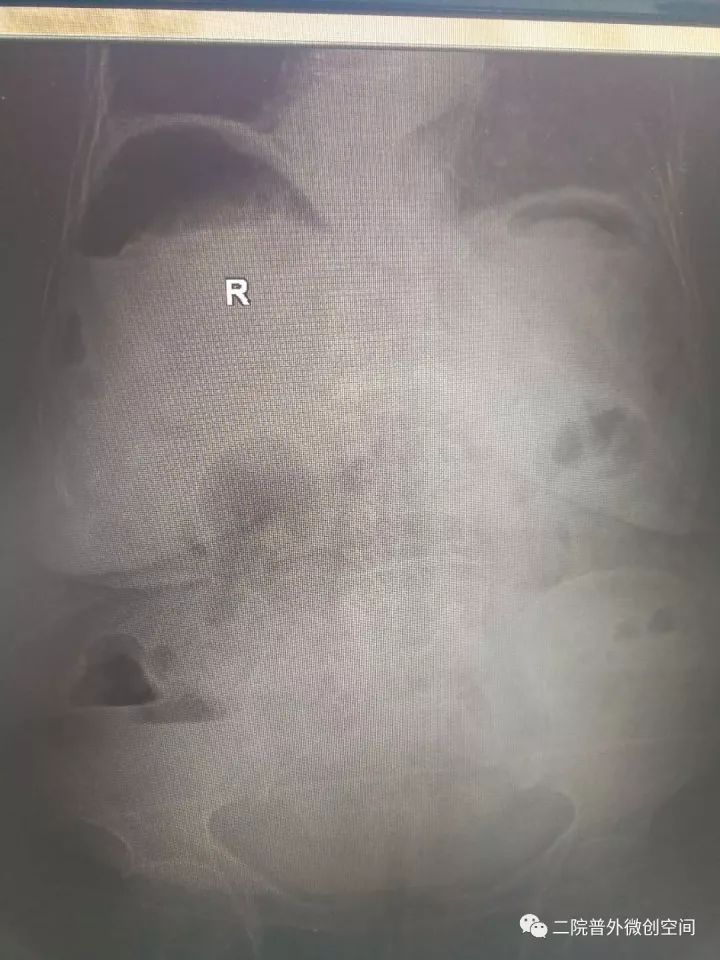

据悉,老奶奶月前摔伤而口服止痛药,2017年10月23日中午突然出现腹痛,逐渐加重,急到当地卫生院就诊,当地医生检视后斟酌“急腹症”急转夏邑县第二人民医院普外科。入院后经副主任医师井晓亮检查后斟酌消化道穿孔,治疗需手术治疗。

经过充分的术前准备,在麻醉科同事保驾护航下告捷为患者施行了腹腔镜下胃穿孔修补术。麻醉及手术过程的艰难程度可想而知——低血压、低血氧、腹腔充满脓液,穿孔大......而这些,在井晓亮主任、谢龙医师、王天琪医师的精细操作下一一化解!